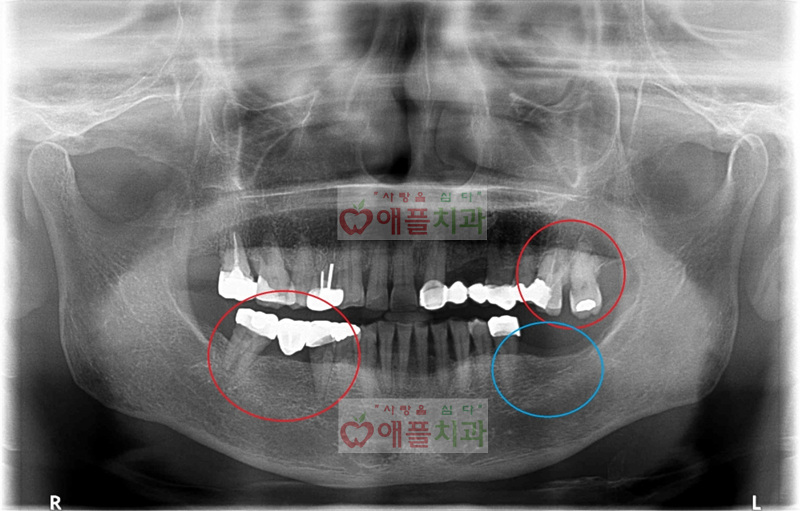

아래의 엑스레이에서 빨간원 부위의 치아가 많이 흔들리고 아파서하셨습니다. 발치후 임플란트 설명드렸습니다.

파란원 부위는 오래전에 이미 발치하셨다고 합니다.

< 우측 아래 임플란트 3개 식립>--------> < 좌측 위 1개, 아래 1개 임플란트 식립>

우측 아래 임플란트 3개를 먼저 수술 하시고 보철까지 마무리 하신다음에 좌측에 위, 아래 수술 진행하셨습니다.